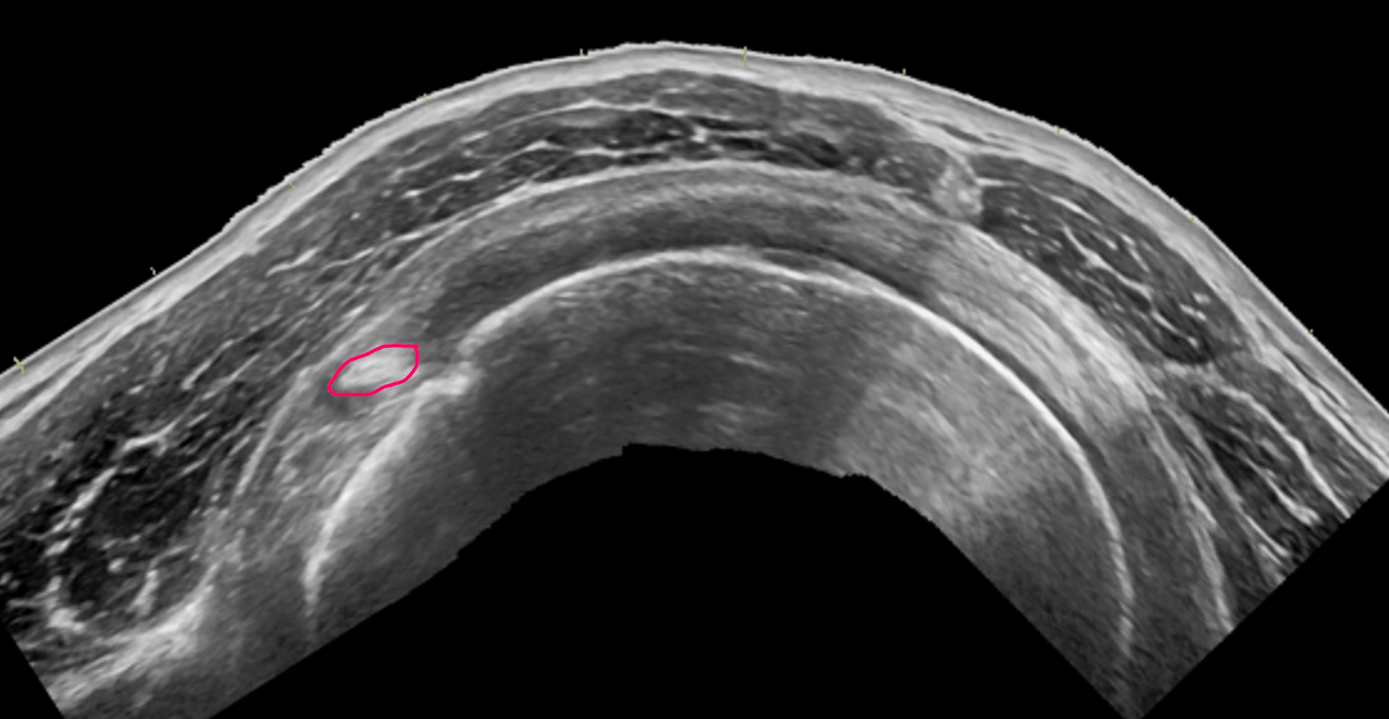

When present this structure may cause ulnar nerve compression at the elbow.

What is an anconeus epitrochlearis?